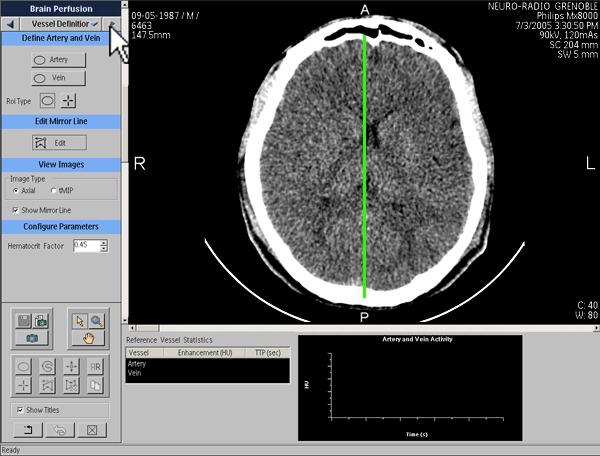

Axe de symétrie

Définition de la fonction d’entrée artérielle

Définition de la fonction de sortie veineuse